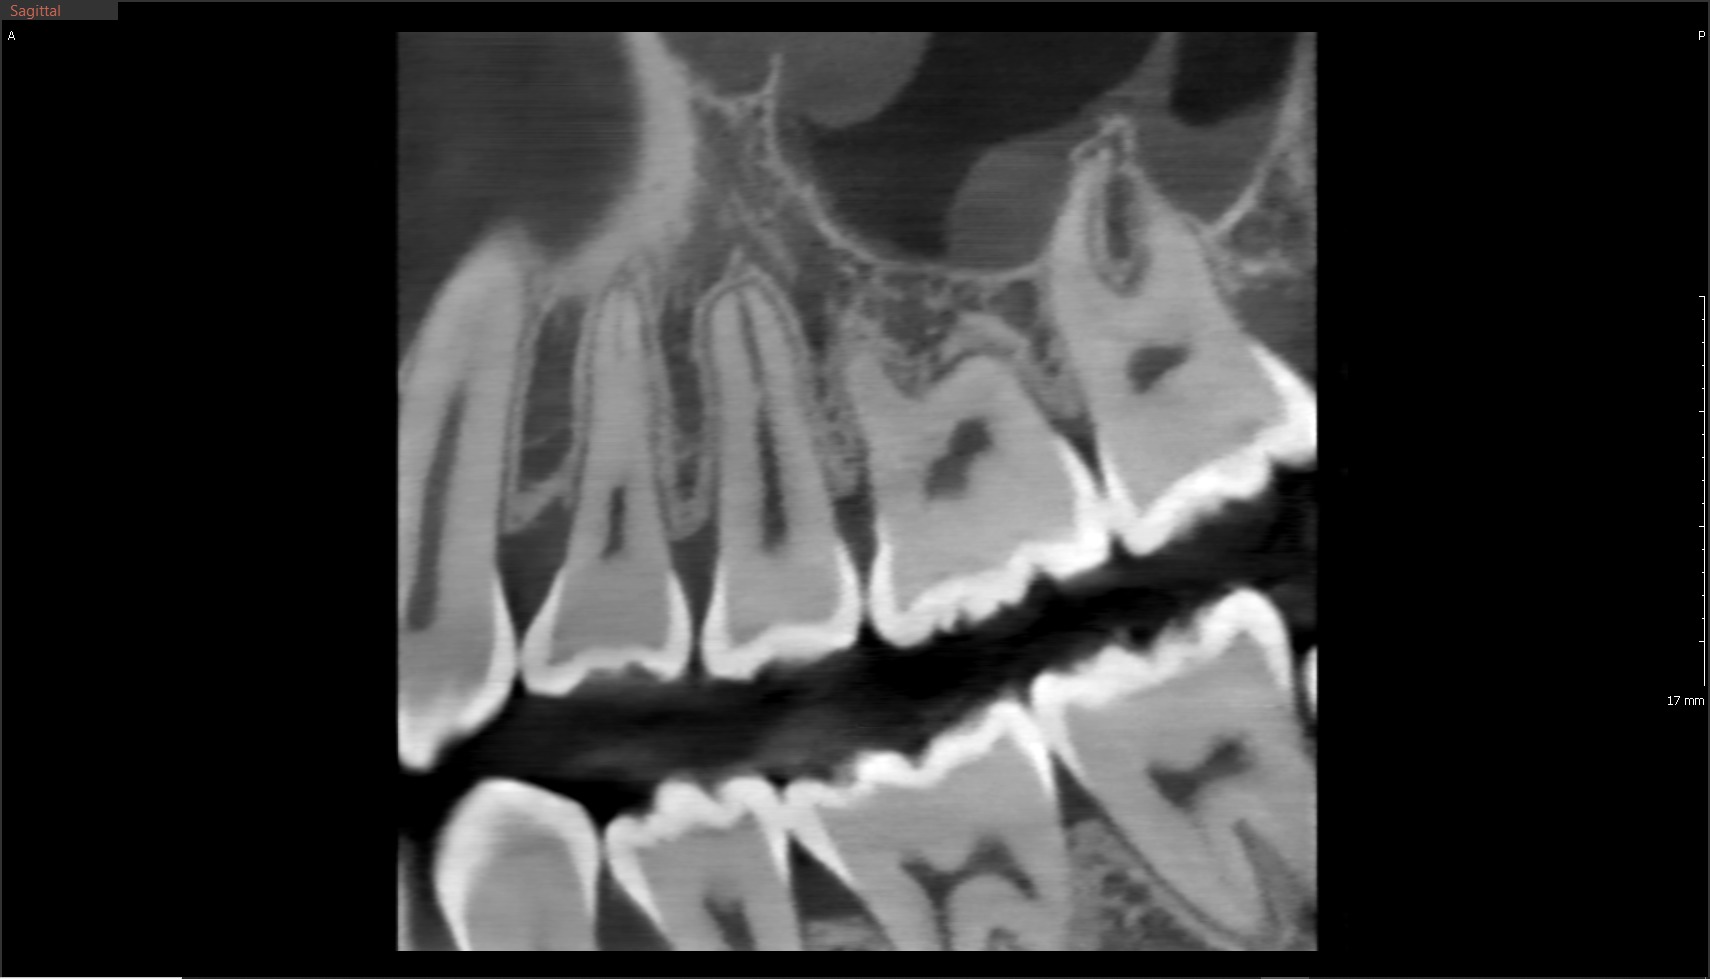

Das Green X ist ein 4-in-1 Röntgenbildgebungssystem der Superlative, welches sowohl 2D-Modalitäten wie Panorama- und kephalometrische Aufnahmen in ultrahochauflösender Bildqualität ermöglicht, als auch flexible 3D-DVT-Aufnahmen von Patienten, Modellen und Abformlöffeln.

• Endo Modus mit höchster Auflösung FOV 4x4; Ultra-High-Resolution 49µm; 3,5 Lp/mm

Green X von orangedental Endo Aufnahme

Höchste Detailschärfe

Das Green X ist mit 49μm bei einem FOV von 4x4 cm das Gerät mit einem der weltweit höchsten Auflösungen und der daraus resultierenden Detailschärfe. Dank der byzzEz3D-i Software mit dem Endo-Modul rekonstruiert diese aus ultrahochauflösenden Schichtaufnahmen perfekte 3D Aufnahmen. Diese können dann als Hologramm in allen drei Dimensionen vermessen werden.

Ein ideales Instrument zur Vorbereitung für jede Wurzelkanalaufbereitung und WSR und auch ein hervorragendes Hilfsmittel zur 3D-Visualisierung, Behandlungsplanung und Patientenberatung.

Eine von vielen Besonderheiten des Green X ist die erweiterte Insight PAN 2.0 Funktion.

Das Insight PAN 2.0 Scan Protokoll (mit 41 Schichten im Multilayer) erlaubt Ihnen Panorama-Aufnahmen für mehr Tiefenschärfe. Diese Funktion begrenzt die Mehrschichtaufnahmen auf die Region, welche durch das Free FOV festgelegt wird. Somit wird die Dosis für den Patienten maximal reduziert und ermöglicht erstmalig Multilayer-Zahnfilm- und Multilayer-Bissflügel-Aufnahmen.

Die Überlagerung der Oberflächenmodelle (STL-Daten) aus externen Scan-Systemen ist durch die exzellente Oberflächendarstellung der 3D-Röntgenaufnahmen problemlos und komfortabel. Somit bietet das Green X alle Möglichkeiten, den digitalen Workflow im Praxisalltag umzusetzen. Eines für alles und alles für Sie!

Green X von orangedental 2D Aufnahme

Zahnerhaltung ist eine der Hauptdisziplinen in der Zahnheilkunde

Hierzu stehen heute der modernen Zahnheilkunde vielfältige Technologien zur Verfügung, um die Zähne endodontisch zu diagnostizieren. Neben der 2D-Radiologie und Mikroskopie ist die DVT-Technologie das wichtigste Diagnosewerkzeug.

Die byzzEz3D-i Software mit dem erweiterbaren Endo-Modul rekonstruiert aus den ultra-hochauflösenden Schichtaufnahmen perfekte 3D-Aufnahmen. Die 3D-Endo-Aufnahmen können als Hologramm in allen drei Dimensionen vermessen werden. Sowohl die Bi- und Trifurkation, Kanalanzahl, Kanalverlauf, Kanallänge und -durchmesser sowie die Krümmungsradien können einfach farblich gekennzeichnet werden. Damit ist das 3D-Endo-Modul nicht nur ein ideales Instrument zur Vorbereitung für die Wurzelkanalaufbereitung und WSR, sondern auch ein hervorragendes Hilfsmittel zur 3D-Visualisierung, Behandlungsplanung und Patientenberatung.